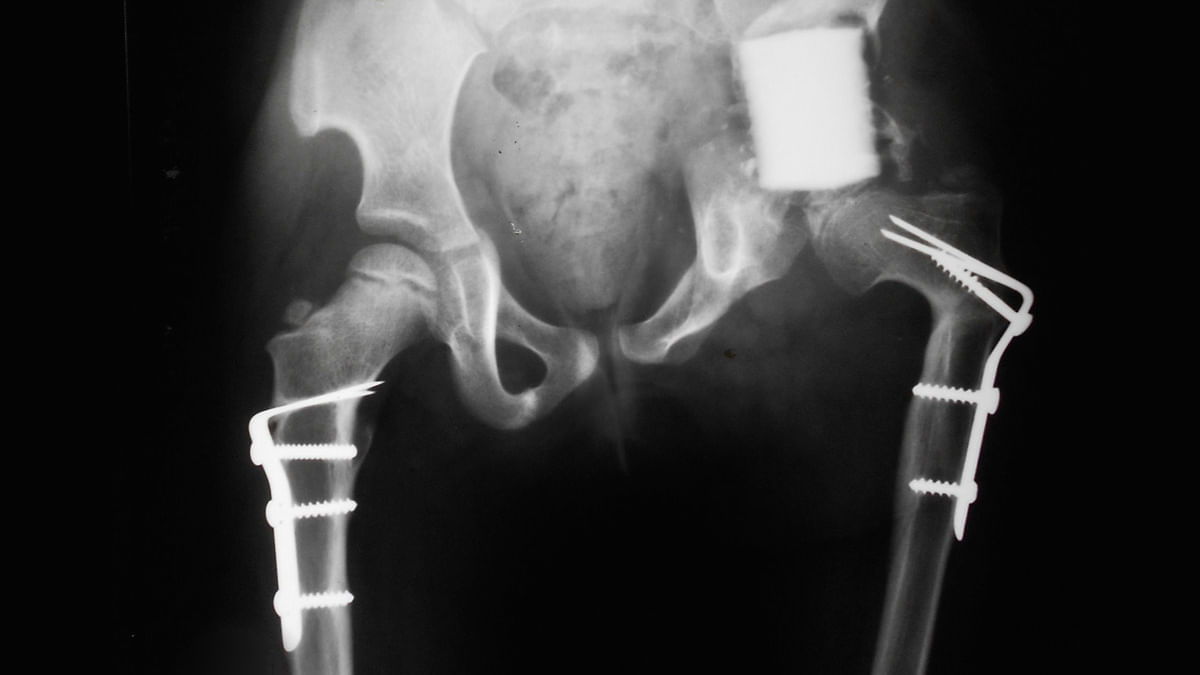

Sie verbringt ihre Tage im Bett. Wenn sie das Haus verlässt, dann nur für kurze Wege, nur mit Hilfe ihrer Krücken. Ihr linker Fuß ist zu einem Fremdkörper geworden, der ihr nicht mehr gehorcht nach all den Operationen. Ihr Rückgrat ist verkrümmt.

Nach jeder neuen OP war die Mutter schlaflos, aber Dr. Burnei schaute auf die Röntgenbilder und sagte: „Das sieht sehr, sehr gut aus!“

Die Jahre vergingen, Amira wuchs zu einer jungen Frau heran, aber ihr linkes Bein wuchs nicht mit. Es ist acht Zentimeter kürzer als ihr rechtes.

„Sehr, sehr gut“, sagte Burnei weiterhin, bis er mit was Neuem kam: Amira braucht einen Fixateur.

Der Fixateur wurde in der Sowjetunion erfunden und ist ein Apparat, der aus Robocops Kleiderschrank stammen könnte. Er besteht aus Metallstäben, einem Dehnungsriegel und Klammern aus Metall oder Karbon, die direkt am Knochen angebracht werden. Der Fixateur wird hauptsächlich eingesetzt, um Gliedmaßen zu verlängern. Zwei Stücke eines Knochens werden auseinandergezogen und die entstandene Lücke soll sich durch das Wachstum neuen Knochengewebes wieder schließen.

Drei Operationen später, die notwendig waren, um den Fixateur zu entfernen und den inzwischen gesplitterten Oberschenkelknochen mit einem Metallstab zu fixieren, fand Emilia ihre Tochter erneut auf der Intensivstation wieder.